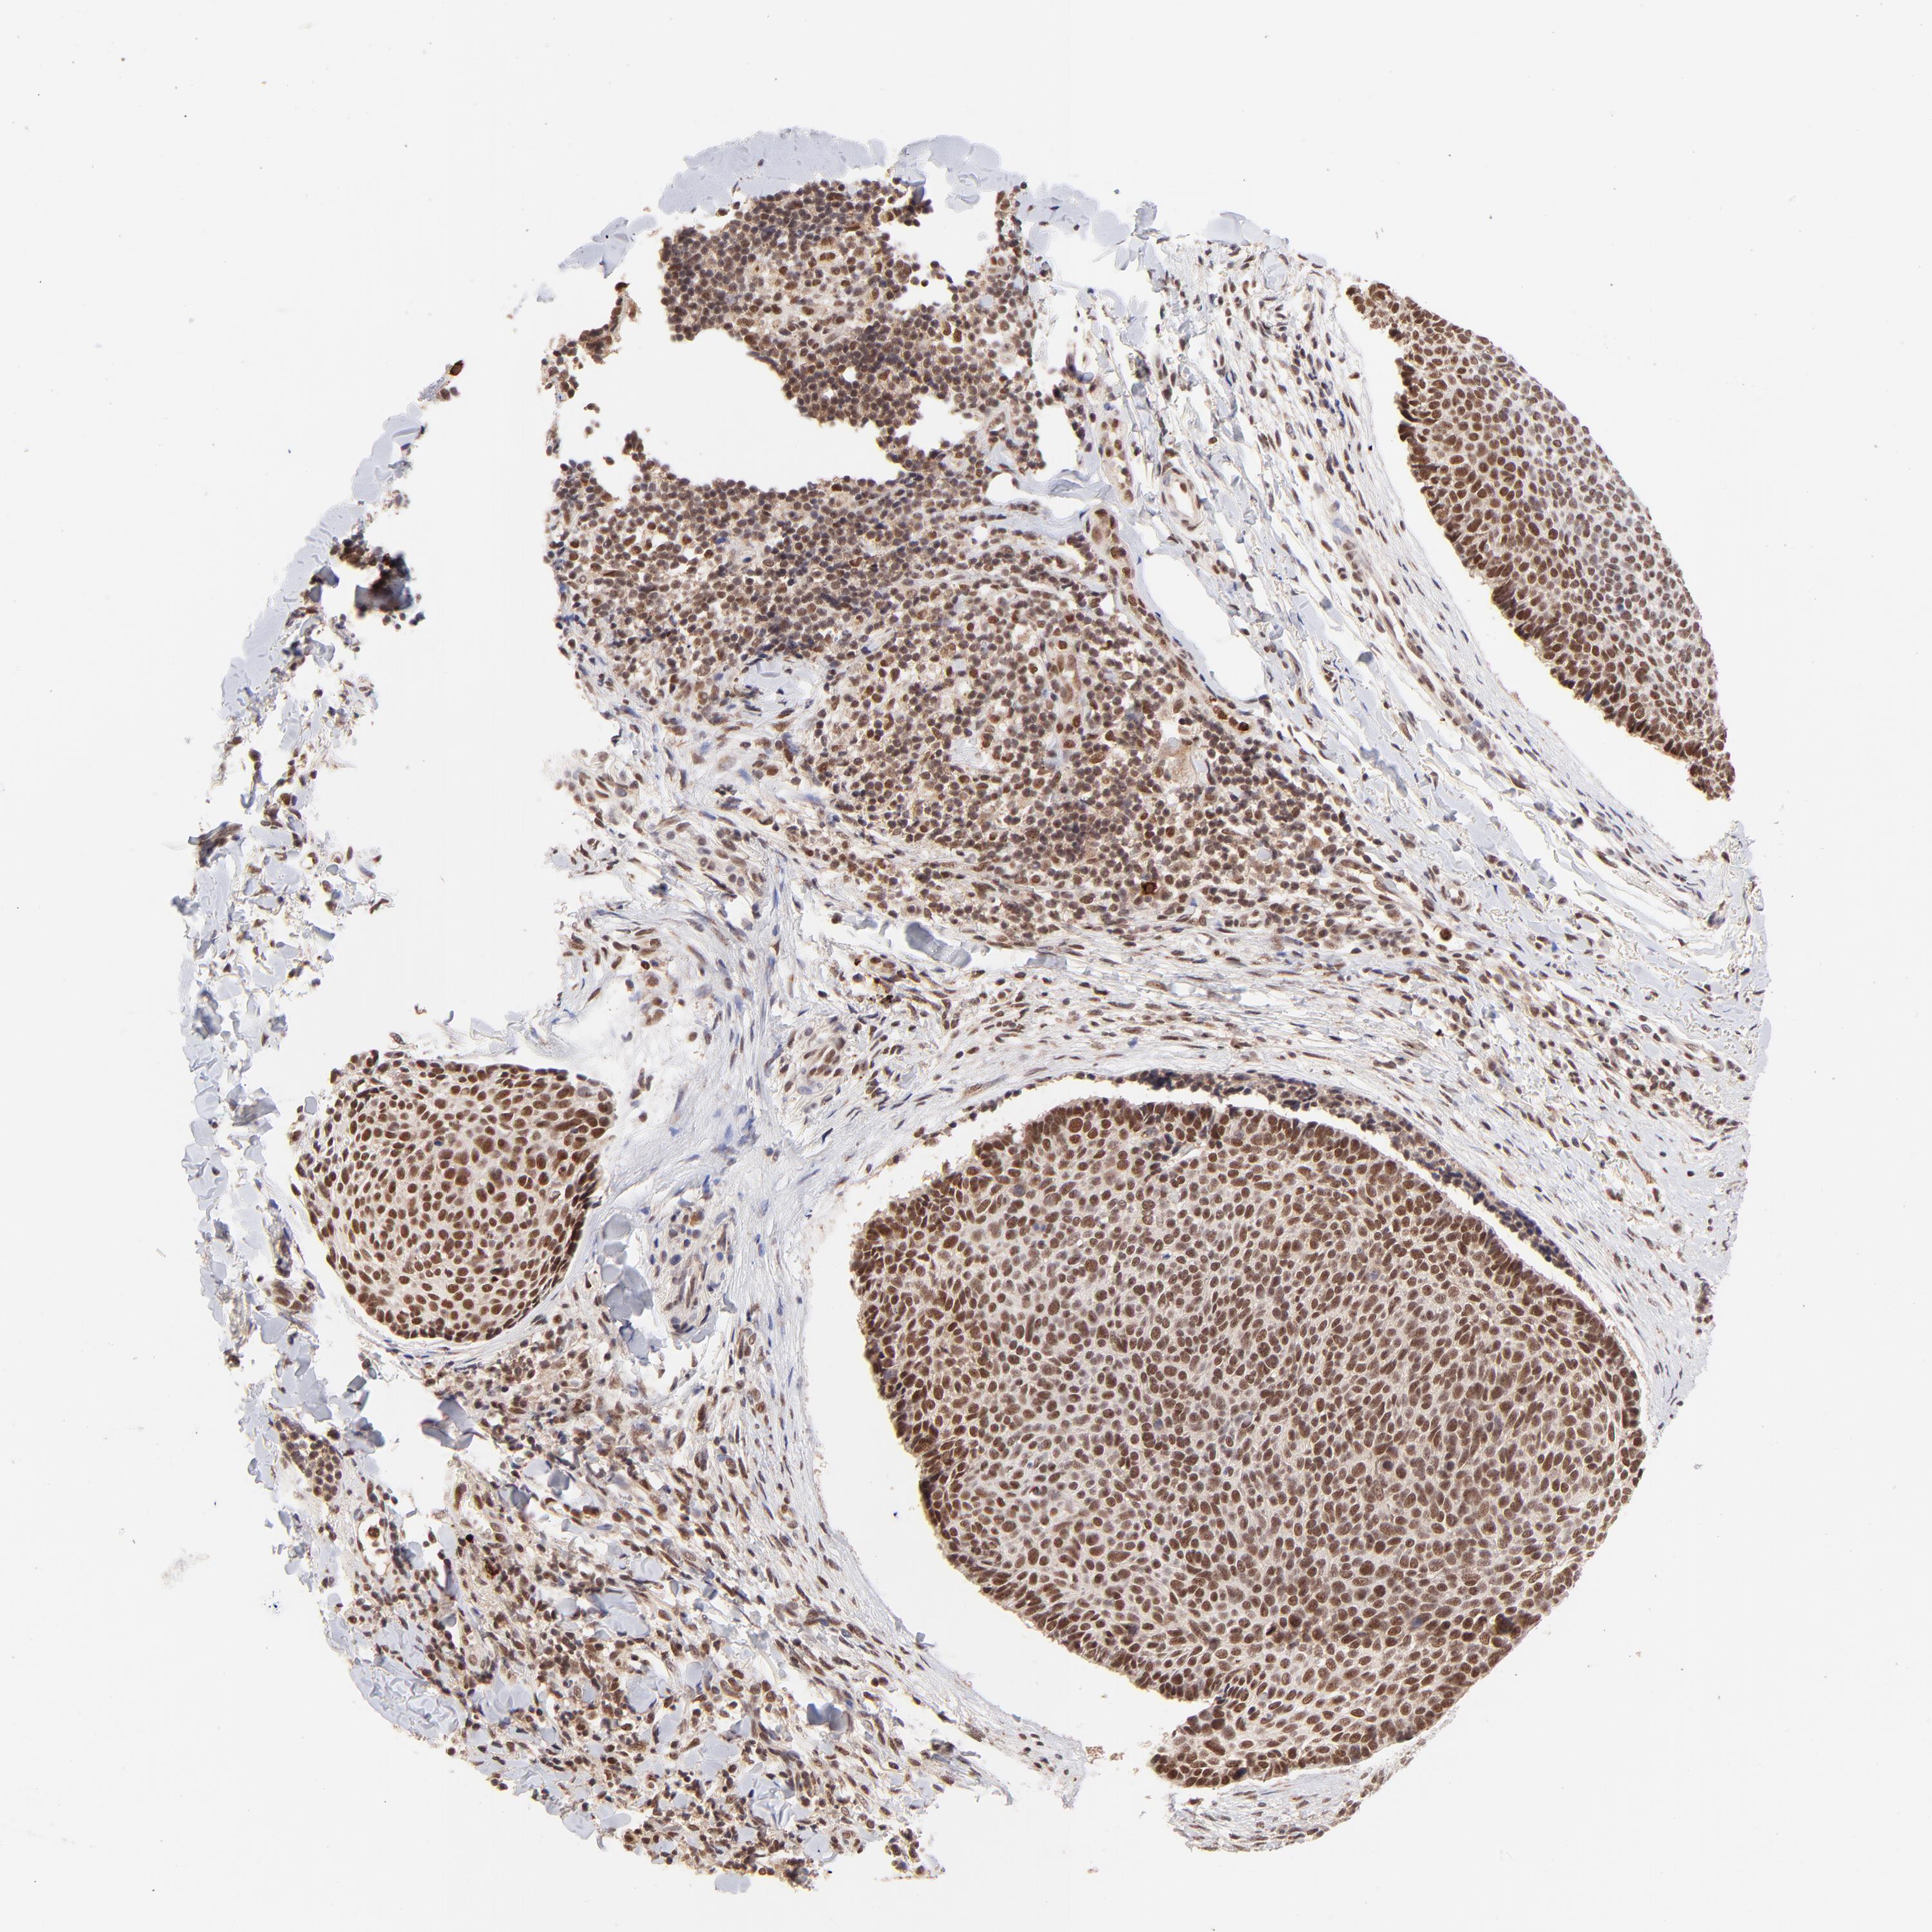

SKIN CANCER - Protein expressioni

A mouse-over function shows sample information and annotation data. Click on an image to view it in a full screen mode. Samples can be filtered based on level of antibody staining by selecting one or several of the following categories: high, medium, low and not detected. The assay and annotation is described here.

Antibody staining in the annotated cell types in the current human tissue is reported as not detected, low, medium, or high, based on conventional immunohistochemistry profiling in selected tissues. This score is based on the combination of the staining intensity and fraction of stained cells.

Each image is clickable and will lead to virtual microscopy that enables deeper exploration of all samples and also displays staining intensity scores, fraction scores and subcellular localization as well as patient and tissue information for each sample.

Antibody HPA003184

Staining

High

Intensity

Strong

Quantity

>75%

Location

Nuclear

Squamous cell carcinoma, NOS

Basal cell carcinoma